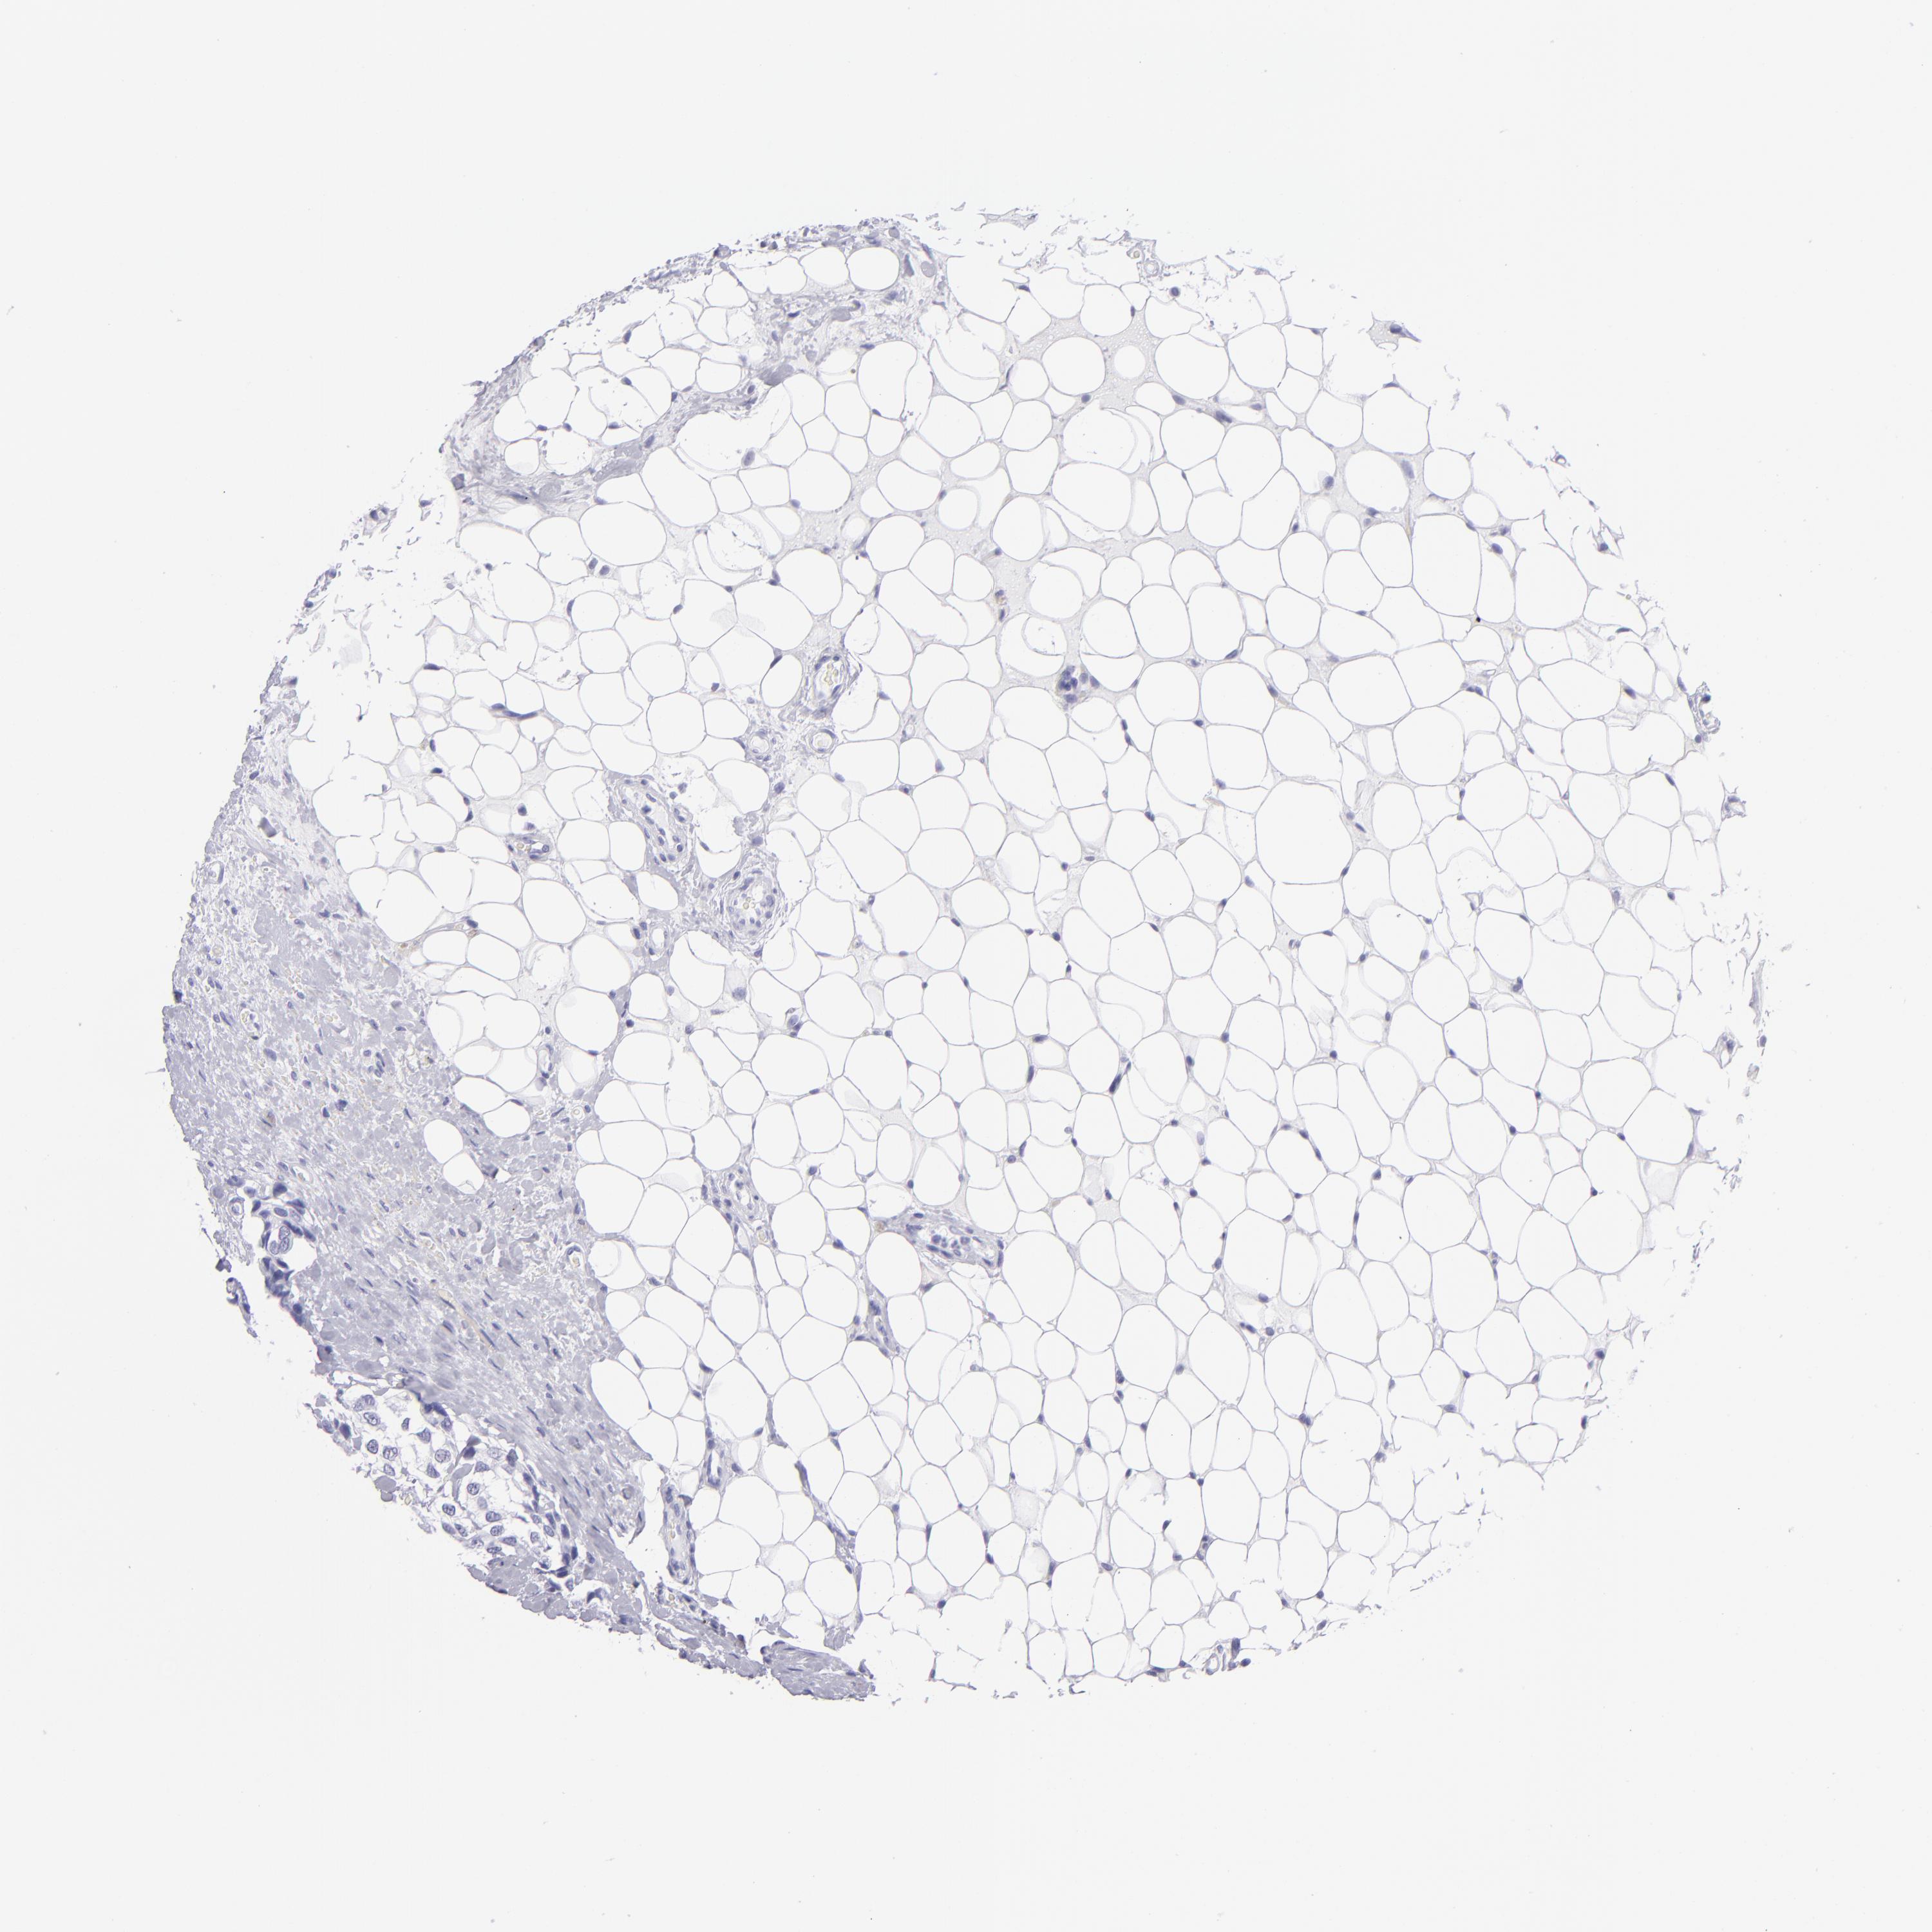

BRCA TCGA BRCA VALIDATION PROTEIN EXPRESSION

ANTIBODIES

AND

VALIDATION